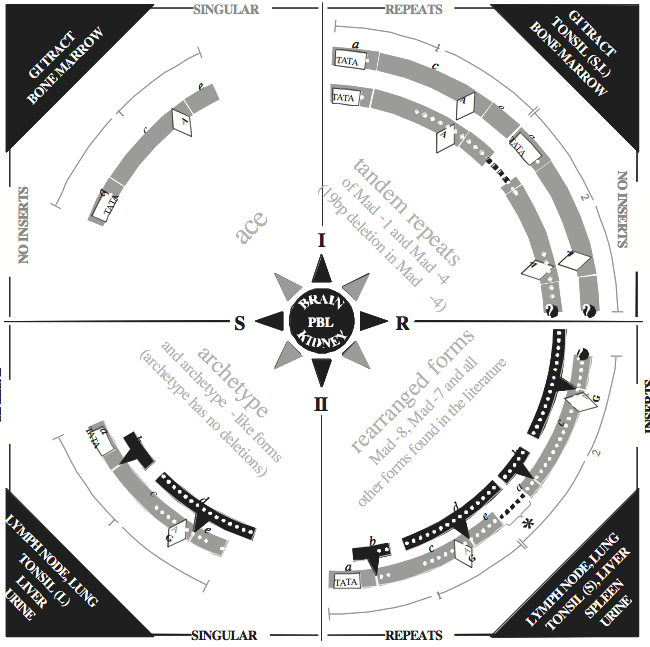

The non-coding regulatory region of each polyomavirus is positioned between the early and late protein-coding sequences. This sequence contains promoter/enhancer elements. Within each polyomavirus species, the nucleotide sequence of the regulatory region is hypervariable. Nucleotide sequencing studies have uncovered numerous variations of regulatory region structure. For the human polyomavirus JCPyV, as with other polyomaviruses, the nucleotide sequence of the regulatory region has been shown to control levels of viral transcription and replication. The JCPyV “archetype” regulatory region sequence, which conveys relatively inefficient viral activity, contains a single copy of all sequence sections observed in all other variant forms (Figure 4). From the early side of the archetype, the initial regulatory region sequence section contains ORI followed by sequence sections designated a, b, c, d, e and f. From variant to variant, sequence sections a through e are the most likely to present deletions, replications and/or unique arrangements; for example, deletion of b and d leaves ace, a 98 bp sequence unit. Although the ace sequence unit conveys more activity than archetype, it appears to be the minimal sequence unit required for function. Also, tandem ace sequence units, or repeats, constitute the regulatory region of the more robust “prototype” JCPyV sequence, Mad-1. Such modification to the regulatory region structure appears to alter the cellular host range and may also be responsible for switching JCPyV between states of lytic and latent infection. Arranging all known variant JCPyV regulatory regions into quadrants, according to integration of unique sequence sections and/or repetition of sequence section groups, also links variants by activity. Four distinct structural forms (I-S, I-R, II-S and II-R) are defined along with tissue tropisms. This design, known as the JCV Compass (Figure 4), provides logical connections between variant regulatory regions and may be useful for elucidating crucial steps in JCPyV pathogenesis. Currently, it is not known whether similar arrangements of other polyomavirus species variants also render logical relationships. The consensus sequence of the regulatory region responsible for binding of large T antigen, including that at ORI, is distinctly different in the avian polyomaviruses from that in the mammalian polyomaviruses.

Figure 4 The Compass: A schematic diagram of the relationships between JC polyomavirus (JCPyV) regulatory region sequences published worldwide. JCPyV variant regulatory regions are grouped into quadrants (I-S, I-R, II-S and II-R) with ace sequence-units lightly shaded. Upper quadrant variant types (I) have no additional sequence integrated into the ace units (no inserts). Lower quadrant variant types (II) have dark integrated sequence sections (inserts), b (23 bp) and d (66 bp). Both types I and II are divided into singular (S) and repeat (R) forms by the left and right quadrants, respectively. Unshaded boxes are TATA boxes. Dots represent sites of possible deletions. Unshaded diamonds contain the nucleotide that occupies the 49th position in sequence section c (nt 85 of I-S, or 108 of II-S), which is adenine (A) in type I variants, but predominantly guanine (G) in type II variants. Right quadrants (R-forms) have dark dashes where sequence is deleted and where additional repeats may occur. The * in the lower right quadrant (II-R) identifies one reported sequence that retains the second TATA box (Ciappi et al., 1999). JCPyV tropism common to all variant regulatory region forms is contained in the dark central circle. Specific JCPyV tropisms are contained in the dark corner triangles. Cells from tonsil are either (L) lymphocytes, or (S) stromal cells (Monaco et al., 1998). Cells in bone marrow that contain JCPyV have been identified as B-lymphocytes

(Houff et al., 1988).